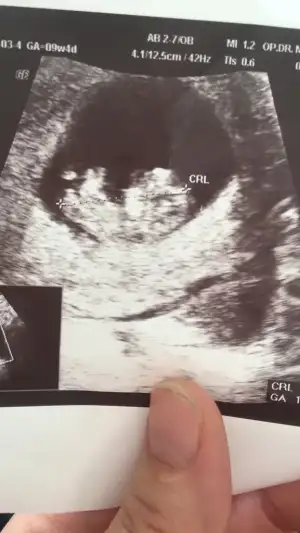

Bana da bakarmısın lütfen 11+4 haftalık 🥰

Acısı 30° canım belkide ileri haftada yükselir başka USG varsa paylaşın 11+4 USG erkekte olabilir 🤗13 haftada nubu tam net olur aslında 🙈 oranları ilk sayfaya yazmıştım